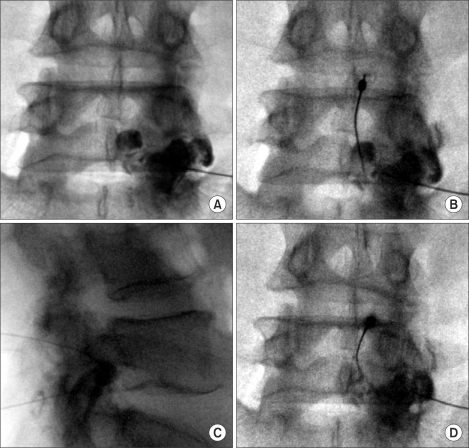

MRI showing L4-5 synovial cyst compressing the thecal sac and right nerve root. Sagittal (left) and axial (right) T2-weighted views demonstrating the cyst arising from the facet joint.

4. Joint entry: Advance a 22-25 gauge spinal needle into the facet joint under fluoroscopic guidance using an oblique or lateral approach

5. Arthrogram: Inject contrast to confirm intra-articular position and visualize the joint capsule and cyst communication

6. Pressurization: Slowly inject additional volume (steroid + anesthetic + contrast, typically 2-4 mL total) to pressurize the joint capsule and rupture the cyst

• Inject 0.1-0.3 mL contrast through microbore tubing with real-time fluoroscopy to confirm intra-articular position

• Contrast typically fills the superior and inferior recesses, creating a dumbbell appearance on AP/oblique views

6. Signs of successful rupture: Loss of tactile resistance to injection, extravasation of contrast from the cyst into the epidural space on fluoroscopy